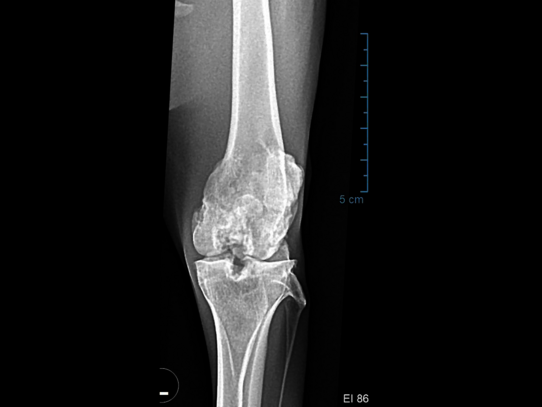

Case 4: Mara

In October 2024, Mara-Dame Orls (born 2022) showed significant lameness in her left hind leg and a sawhorse stance. In collaboration with a specialist veterinarian from the Ludwigsburg-Oßweil Small Animal Clinic, an examination was performed under anesthesia. The X-ray revealed osteoarthritis of the left knee joint. A fine needle aspiration was performed to rule out a tumor – with negative results. Nevertheless, her condition continued to deteriorate: withdrawal, loss of appetite, and immobility despite pain therapy. After careful consideration of various options, euthanasia was ultimately unavoidable. The autopsy revealed severe osteochondrosis dissecans with chronic arthritis and synovitis.